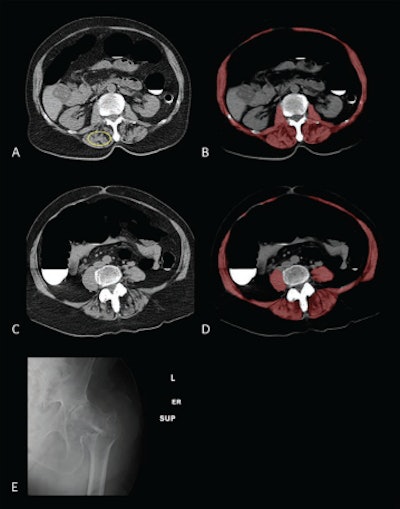

Sarcopenia (myosteatosis) at screening CT colonography in a 79-year-old woman with subsequent hip fracture. Image at L1 vertebral level without (A) and with (B) overlay of automated skeletal muscle segmentation (B, red). Intramuscular fat is present within paraspinal muscles (A, yellow circle). Mean muscle attenuation is similar for manually placed ROI (1.8 Hounsfield units [HU]) and automated tool (3.9 HU), being markedly decreased for both approaches. Muscle cross-sectional area is relatively preserved when intramuscular fat is included. CT images at L3 level without (C) and with (D) muscle segmentation demonstrate similar findings. E. Hip radiograph demonstrates left intertrochanteric femoral fracture that occurred when the patient fell two years later. The patient died four years after falling. Images courtesy of the American Journal of Roentgenology.The researchers also noted that the muscle cross-sectional area measurements at both L1 and L3 were less predictive of hip fracture and death than the muscle attenuation measurements and clinical risk scores. These muscle area measurements produced a five-year AUC of 0.521 and 0.571, respectively, for hip fracture, and 0.536 and 0.544, respectively, for death.